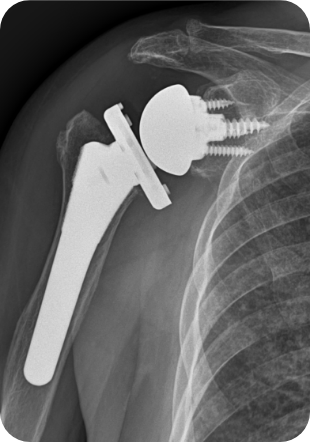

상완골두만을 갈아끼우는 반치환성형술을 할 수도 있고, 견갑관절과 인공삽입물이 함께 삽입되는 전치환성형술을 하기도 합니다. 최근에는 역 전치환술이 개발되어 기존 인공관절의 단점을 보완하게 되었습니다.

• ▲ 어깨인공관절 인공치환술 전

• ▲ 어깨인공관절 인공치환술 후